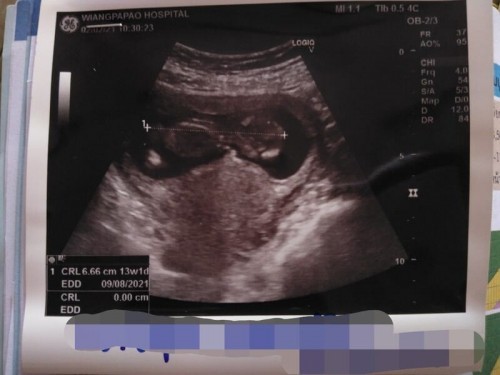

ภาพซาวด์ตอน 13+1 ค่ะ มีคนเดียวแต่เหมือนแฝด

ภาพนี้เพิ่งซาวด์มาเมื่อวันอังคารค่ะ หมอบอกมีคนเดียวและก็เชื่อหมอค่ะ แต่หลาย ๆ คนบอกว่าเหมือนแฝดค่ะ อยากทราบความเห็นของแม่ ๆท่านอื่นค่ะ#ท้องแรกค่ะ #ขอบคุณล่วงหน้านะคะ

ถ้ามีสองคนยังไงก็ดูออกค่ะเพราะ13wอวัยวะครบหมดเเล้ว เเล้วลูกคงไม่ทับกันค่ะ ภาพนี้ดูยังไงก็คนเดียวจ้าเเม่

น่าจะเป็นส่วนหัวกับลำตัวนะคะ 13วีคยังแบ่งไม่ชัด รออีกสักเดือนน่าจะแน่ใจว่าลูกคนเดียวหรือแฝด

ค่ะ วันนี้เพิ่งไปตรวจท้องมาอีกรอบ คนเดียวชัดเจนค่ะ

ถ้าแฝดจะมีถุงน้ำคล่ำ 2 ใบค่ะ

เป็นส่วนหัวกับลำตัวค่ะ